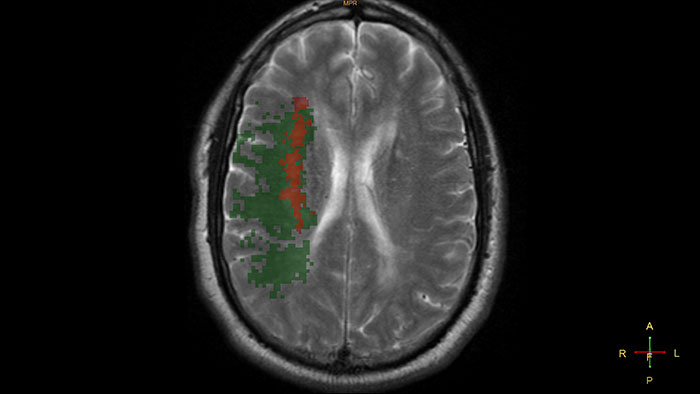

Longitudinal Brain Imaging (LoBI)

MR Longitudinal Brain Imaging (LoBI)

Gain an optimized view of the body’s most complex organ

Supports the visualization of brain images for the evaluation and monitoring of changes across multiple time points. The application performs automatic registration between studies and provides semi-automatic segmentation and editing tools for volumetric measurement of brain lesions.

longitudinal brain imaging thumbnail

Benefits

• The Comparative Brain Imaging feature uses bias field-correction, intensity scaling, image registration and mathematical subtraction to provide color-coded images highlighting subtle brain changes over time.